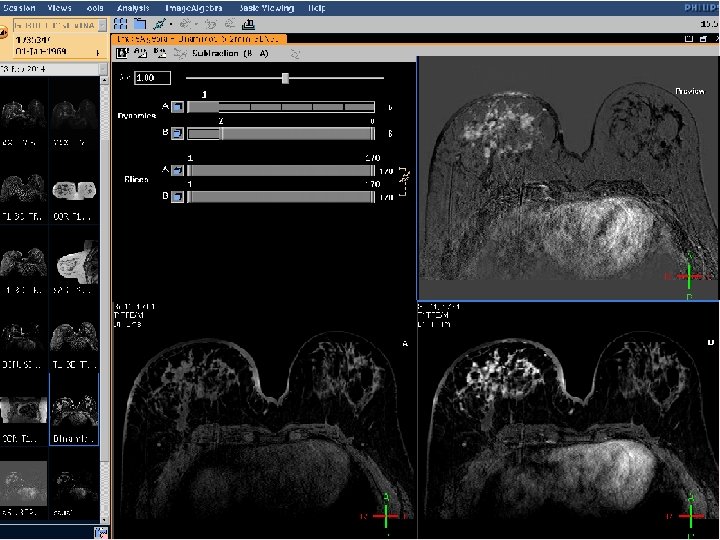

TECNICA DE SUSTRACCION

RESULTADO SUSTRACCION